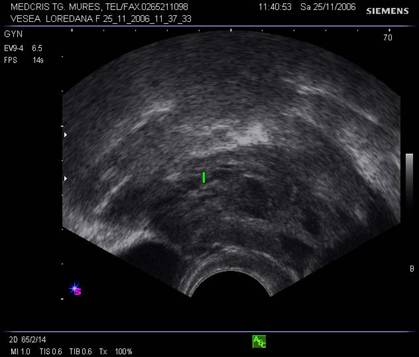

Fig. Nr.358. Uter in sectiune longitudinala, in anteversoflexie